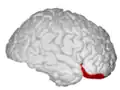

Lateral orbitofrontal cortex -